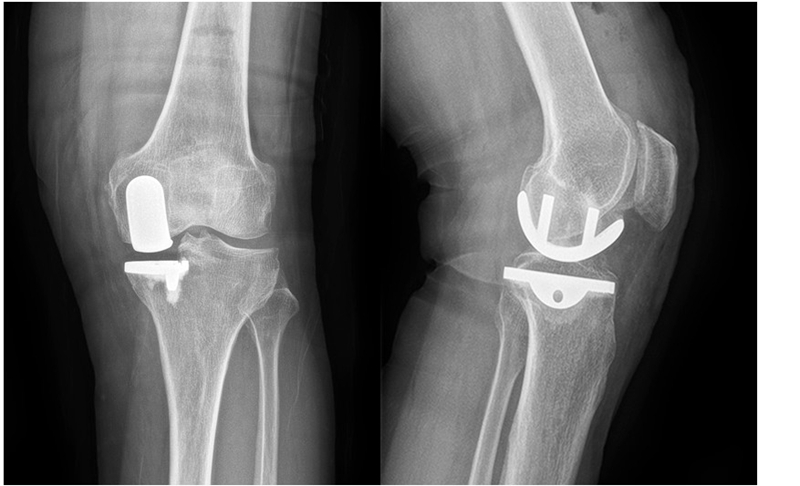

(1)70岁女性患者,以左膝关节疼痛5年、加重1年为主诉入院,入院查体左下肢内翻畸形11°,膝关节内侧间隙压痛阳性,外侧无压痛,髌骨研磨试验阴性,抽屉试验阴性,ROM 5°~120°,诊断左膝关节前内侧骨关节炎,行左膝关节内侧固定平台单髁置换术。术后给予预防感染、消肿止痛及抗凝治疗,术后24h康复师指导助行器辅助下床活动,术后1个月膝关节 HSS评分由63分升至85分,KSS评分由49分升至80分,内侧疼痛消失,患者恢复满意。手术前后影像学资料见图1~2。

图1术前 X线片示内侧间隙呈骨对骨改变

图2术后 X线片示假体位置良好,大小合适